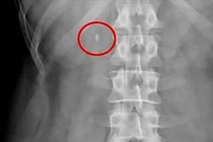

"흡연이 허리 통증도 악화…디스크 발생 위험 최대 1.42배"

흡연이 척추 질환에도 악영향을 끼쳐 디스크 발생 위험을 높인다는 연구 결과가 나왔다. 매일 액상형 전자담배를 사용하는 흡연자는 비흡연자에 비해 척수 디스크 발생 위험이 최대 1.4배에 달했다. 강남세브란스병원 정형외과 권지원 교수와 세브란스병원 정형외과 신재원 교수 연구팀은 국민건강보험공단 자료를 토대로 20세 이상 326만5천여명의 흡연 습관과 척추 디스크 발생의 상관관계를 분석해 이 같은 사실을 확인했다고 11일 밝혔다. 연구는 2019년 1월부터 6월까지 국가건강검진을 받은 20세 이상 성인을 추린 뒤, 검진 후 약 3.5년간 이들의 축적된 흡연 습관과 척추 디스크 발생 위험을 추적 관찰하는 방식으로 이뤄졌다. 연구팀은 이들을 ▲ 비흡연군 ▲ 일반담배 흡연군 ▲ 궐련형 전자담배 흡연군 ▲ 액상형 전자담배 흡연군으로 분류해 분석했다. 척추 디스크는 의사로부터 명확히 진단받아 외래 진료를 2회 이상 받거나, 입원한 기록이 있는 경우에만 환자로 한정해 살폈다. 그 결과 모든 흡연군이 비흡연군에 비해 척추 디스크 발생 위험이 높았고, 일반담배에서 전자담배로 바꿔도 그 위험은 크게 줄어들지 않았다. 비흡연군을 기준으로 했을 때 디스크 발생 위험은 일반담배 흡연군